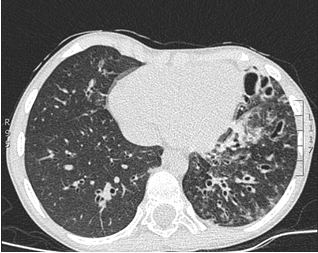

Al momento del examen físico se encontró un niño enflaquecido, con disminución del diámetro anteroposterior del tórax, crépitos finos, sibilancias y roncus difusos en ambos campos pulmonares, con acropaquia incipiente. Por la sospecha de neumopatía crónica se solicitó tomografía de tórax de alta resolución, que mostró la pérdida de volumen del pulmón izquierdo y múltiples bronquiectasias (Figura 3), espirometría pre y posbroncodilatador con alteración restrictiva moderada. La ecocardiografía, estudios para tuberculosis, fibrosis quística e inmunodeficiencias primarias y secundarias fueron negativos. La cine radiografía de la deglución reveló el trastorno de la deglución severo en la fase faríngea y los episodios de bronco aspiración silente.